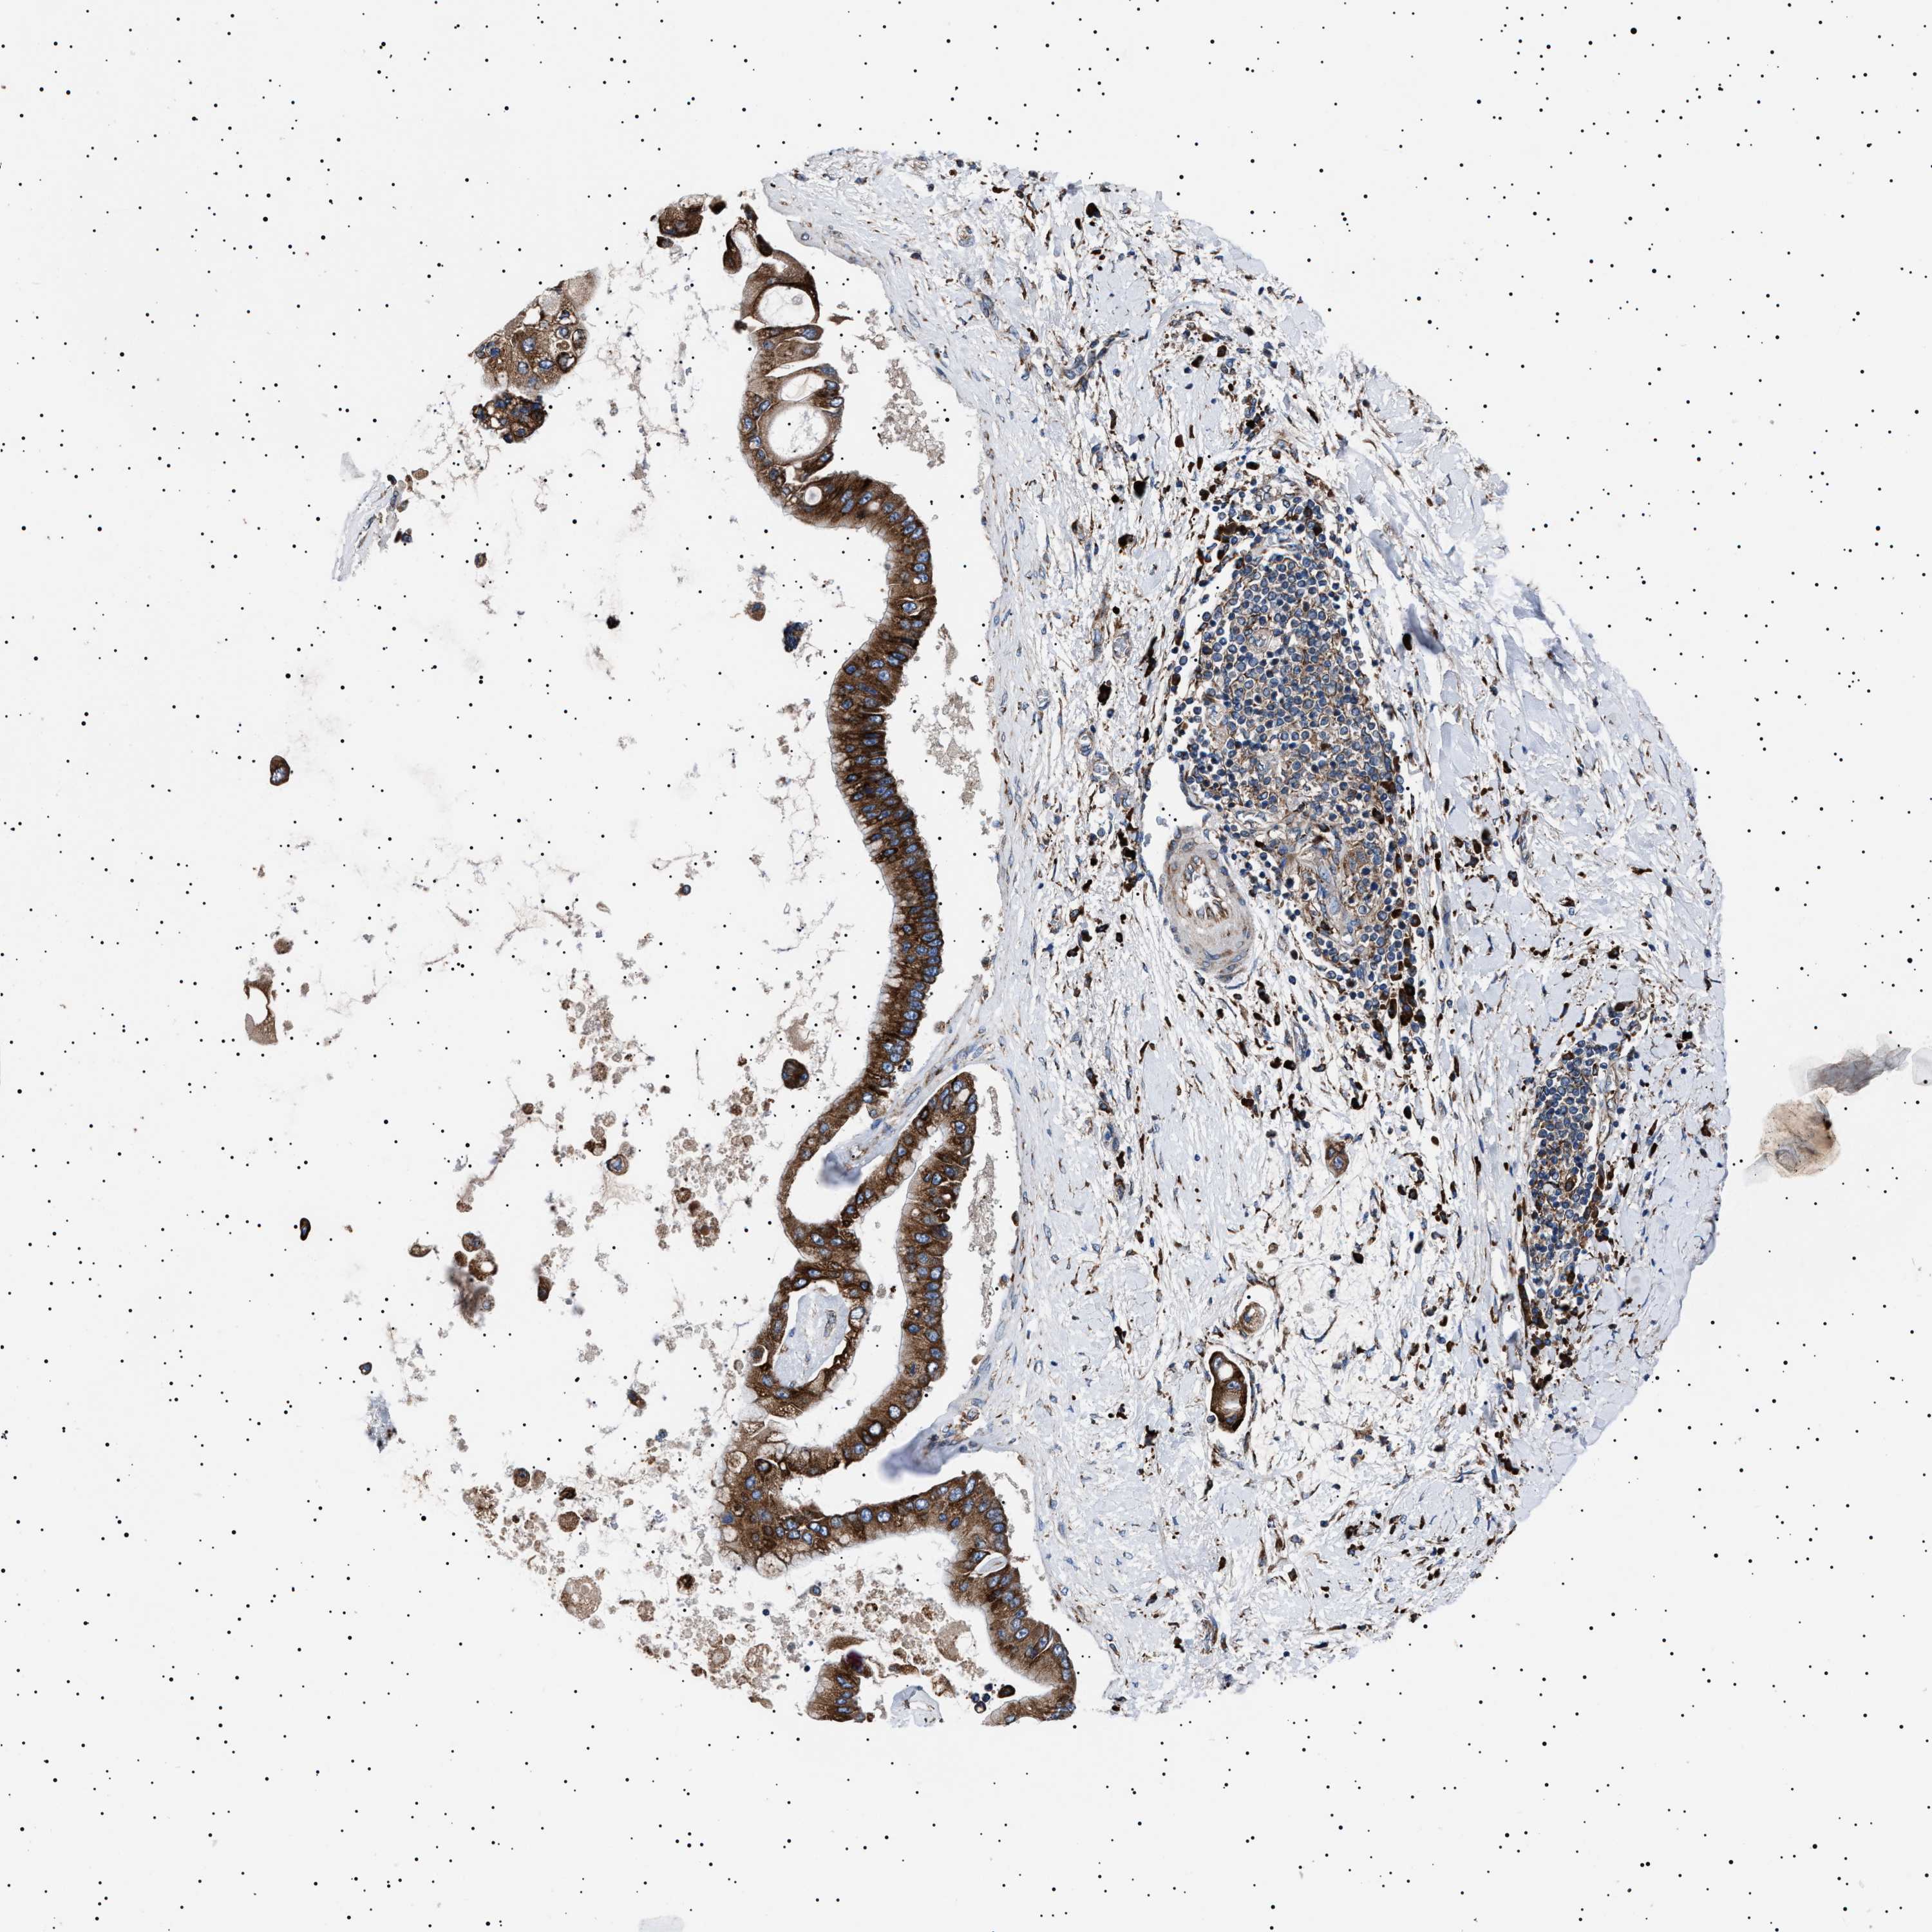

LIVER CANCER - Protein expressioni

A mouse-over function shows sample information and annotation data. Click on an image to view it in a full screen mode. Samples can be filtered based on level of antibody staining by selecting one or several of the following categories: high, medium, low and not detected. The assay and annotation is described here.

Note that samples used for immunohistochemistry by the Human Protein Atlas do not correspond to samples in the TCGA dataset.

Antibody stainingi

Antibody staining in the annotated cell types in the current human tissue is reported as not detected, low, medium, or high, based on conventional immunohistochemistry profiling in selected tissues. This score is based on the combination of the staining intensity and fraction of stained cells.

Each image is clickable and will lead to virtual microscopy that enables deeper exploration of all samples and also displays staining intensity scores, fraction scores and subcellular localization as well as patient and tissue information for each sample.

Antibody HPA001915

Antibody HPA021542

Staining

High

Medium

Low

Not detected

Intensity

Strong

Moderate

Weak

Negative

Quantity

>75%

75%-25%

<25%

None

Location

Nuclear

Cytoplasmic/membranous

Cytoplasmic/membranous,nuclear

Cholangiocarcinoma

Carcinoma, Hepatocellular, NOS